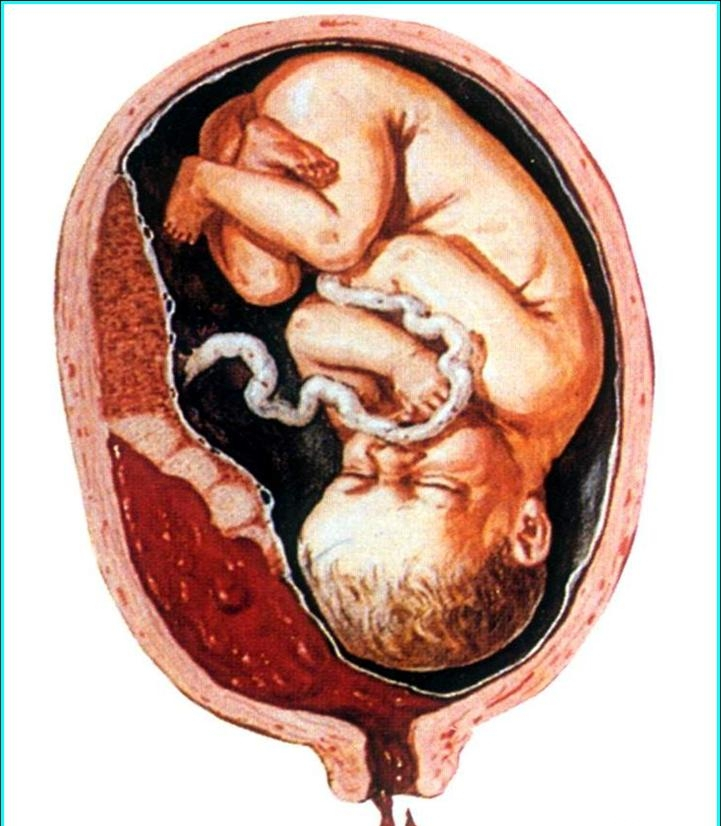

A:胎盤早剝是指在胎兒娩出之前胎盤就從子宮壁上剝離,這是產科比較危險的情況,因為有可能造成大出血,也可能引起胎兒缺氧,也就是胎兒窘迫,再嚴重的可能會發生凝血功能的障礙,甚至有威脅生命的可能性。正常情況下是先有宮縮,宮縮之後可以使宮口逐漸打開,……

A:胎盤早剝是指懷孕20周後,正常位置的胎盤在胎兒娩出前部分或者全部從宮腔壁剝離,發展非常迅速,如果處理不及時會危及母嬰的健康。其典型的臨床症狀是腹痛、陰道出血,可伴有子宮張力增高和子宮的壓痛、反跳疼,尤其是胎盤附著處是最明顯的。陰道出血的特徵……

A:胎盤早剝是女性懷孕滿20周以後,或者是在臨產後,在胎兒分娩出來之前,部分或者整個胎盤從子宮壁剝離下來。根據剝離面積不同,臨床表現也不一樣,剝離面積小的女性可以表現為腹部輕微疼痛,陰道出血比較多,呈現暗紅色,可以伴有大量的血塊。剝離面積大者,……